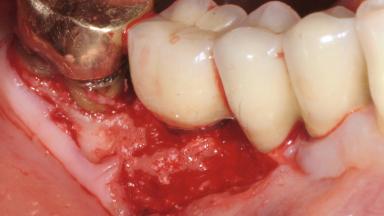

Late Presentation of Peri-Implant Mucositis Requiring Soft-Tissue Augmentation and Esthetic Crown Lengthening at Implant Site 11

Biological or technical complications around implant-supported prostheses place a significant burden on patients as well as the surgical and restorative team. Inflammation of the peri-implant soft tissues is often the first sign that something has gone awry. While there is never a good time for a complication, late presentation of inflammation in the soft tissues around a long-standing prosthesis triggers a period of research and review of the case in order to ascertain the treatment history and its possible contribution to the etiology of the situation. This becomes more complicated in situations where a patient has not received regular maintenance and clinical/radiographical examinations due to personal, financial, or professional reasons. When the complication occurs in the esthetic zone, the complexity of the situation expands exponentially, as the only acceptable outcome in the patient’s eyes will be the maintenance of the esthetics of the prosthesis.